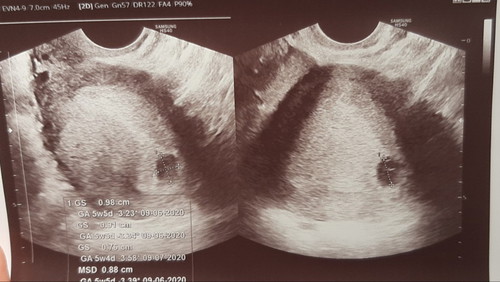

Had my first check up today! Edi ang bilang nga po usually compute sa pregnancy ay sa last mens. po diba, edi dapat 8weeks and 1day na po ako. Ngayong nagpa transv po ako, ang lumabas ay 5weeks 5days pa lang po ako. (Siguro dahil nga daw po sa irregular ako) And wala pa pong signs ng kahit ano maliban sa sac. May makikita na po ba after 2weeks? May possible po ba talaga na walang magiging development after lahat ng vitamins? ?